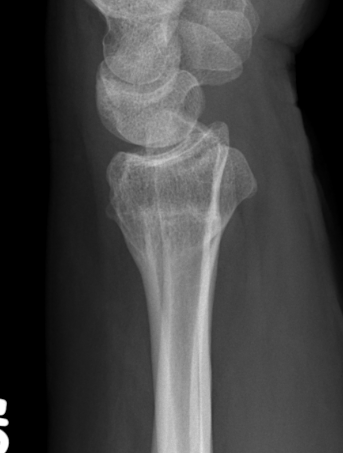

Malunion

| Radial shortening | Radial inclination | Positive ulna variance |

| Dorsal tilt > 15 degrees | Volar tilt > 10 degrees | Articular step > 3 mm |

Pathology

Radial shortening

- affects normal kinematics of the DRUJ

- ulnocarpal abutment

Dorsal tilt

- loss of flexion

- +/- midcarpal instability - DISI / CIND without interosseous ligament disruption

Xray

Bilateral xrays

PA film in neutral

- wrist neutral

- elbow & shoulder at 90°

CT